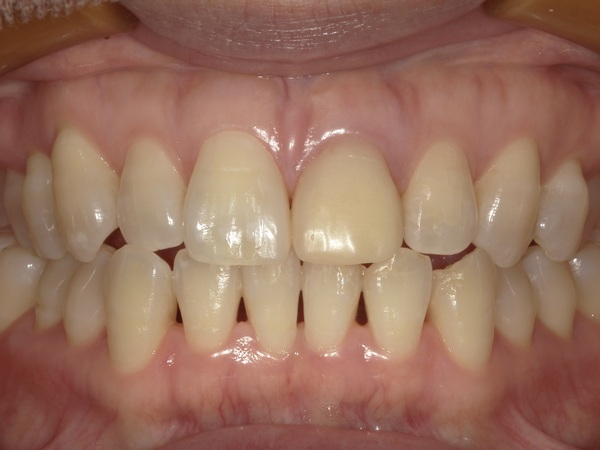

微調整を行い装着しました。こちらがセット後の写真になります。

患者様は、もともとのすきっ歯も改善され、自然な見た目となり、最初より綺麗になったと大変満足されております。また、治療期間は長くかかりましたが、両サイドの歯を削らずに審美的な治療ができたことにもとても喜ばれております。現在は年に2~3回メインテナンスで通院されております。

今回のケースでは歯間乳頭(歯と歯の間の三角形の歯茎)もしっかり維持されており、どの歯がインプラントにしたのかはほとんど分からないと思います。